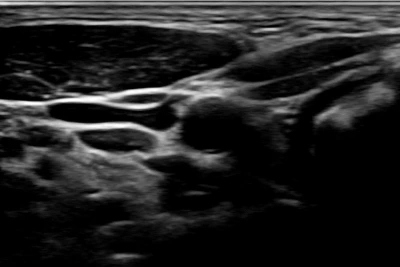

아래는 뇌혈류 초음파 (TCD, Transcranial Doppler)에 대한 검사 결과예요.

뇌혈류 초음파 (TCD, Transcranial Doppler)

검사 목적 : 뇌혈관의 혈류 속도, 방향, 혈관 협착(좁아짐) 여부 평가

tempImageE3NLlX.heic

tempImage5UoUr3.heic

뇌혈류 초음파 사진